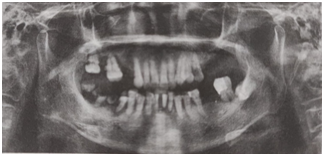

女,72歲。要求行上下頜活動義齒修復。檢查:右上56、左上67、左下6缺失:右上7、右下5、左下12松動Ⅲ度;右上8遠中鄰面齲,不松動,叩痛(-);左上5近中齲壞,不松動,叩痛(+);左下7(牙合)面及近中可見大面積金屬充填物,探及繼發(fā)齲,叩痛(-),不松動,伸長明顯;右下12松動I~Ⅱ度;右下4伸長,松動Ⅰ度;右下67殘根;口腔衛(wèi)生差,余留牙可見大量牙石,牙齦紅腫。曲面斷層片如圖所示。在上下頜行活動義齒修復前準備工作正確的是

【答案解析】修復前準備包括拔除殘根,拔除Ⅲ度松動牙,松動I~Ⅱ度牙齒不應拔除,故A項錯誤;而對于左下8骨埋伏牙,不影響義齒修復,不用拔除,所以選項B錯誤;對于過度伸長牙齒,根療后應大量磨改并行人造冠修復調(diào)整(牙合)曲線,故選項C中依照原有高度行冠修復是錯誤的;對于大面積缺損患牙應行人造冠修復,故D項中左上5牙根管治療后直接樹脂充填治療錯誤;修復前牙周病患者需行牙周治療,此外,余留牙應行咬合調(diào)整以改善平面,故E正確。